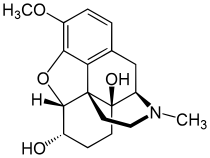

Structures

| Morphides | ||||

|---|---|---|---|---|

Codeine Codeine |

Morphine Morphine |

Oripavine Oripavine |

Pseudomorphine Pseudomorphine |

Thebaine Thebaine |